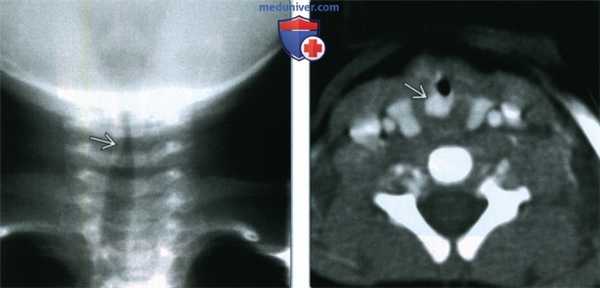

(Слева) Рентгенография в прямой проекции. Асимметричное сужение подскладочного отдела трахеи у младенца двух месяцев со стридором. Асимметричное сужение всегда должно насторожить врача в отношении гемангиомы, поскольку при крупе просвет будет сужен симметрично.

(Справа) КТ с КУ, аксиальная проекция, тот же пациент. Накапливающая контраст гемангиома расположена вдоль заднелатерального края подскладочного отдела.

2. Рентгенография при младенческой гемангиоме верхних дыхательных путей:

• Асимметричное сужение просвета трахеи на прямых снимках

3. КТ при младенческой гемангиоме верхних дыхательных путей:

• Чаще всего единичное, накапливающее контраст образование